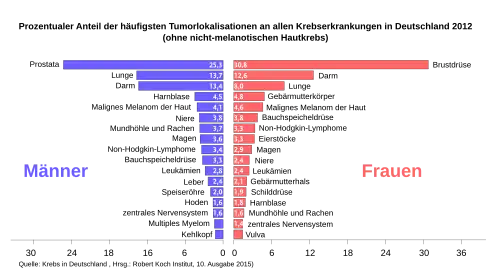

Prinzipiell kann jedes Organ des menschlichen Körpers von Krebs befallen werden. Es gibt jedoch erhebliche Häufigkeitsunterschiede nach Alter, Geschlecht, kollektiver Zugehörigkeit, geographischer Region[2], Ernährungsgewohnheiten und ähnlichen Faktoren. Es gibt über 100 verschiedene Krebsformen. In Deutschland treten Krebserkrankungen gehäuft in Organen wie Brustdrüse (Frauen), Prostata (Männer), Lunge und Dickdarm auf.

Auf der x-Achse die altersstandardisierte Mortalitätsrate (erster Zahlenwert) und der prozentuale Anteil an den Krebserkrankungen (zweiter Zahlenwert in der Klammer).